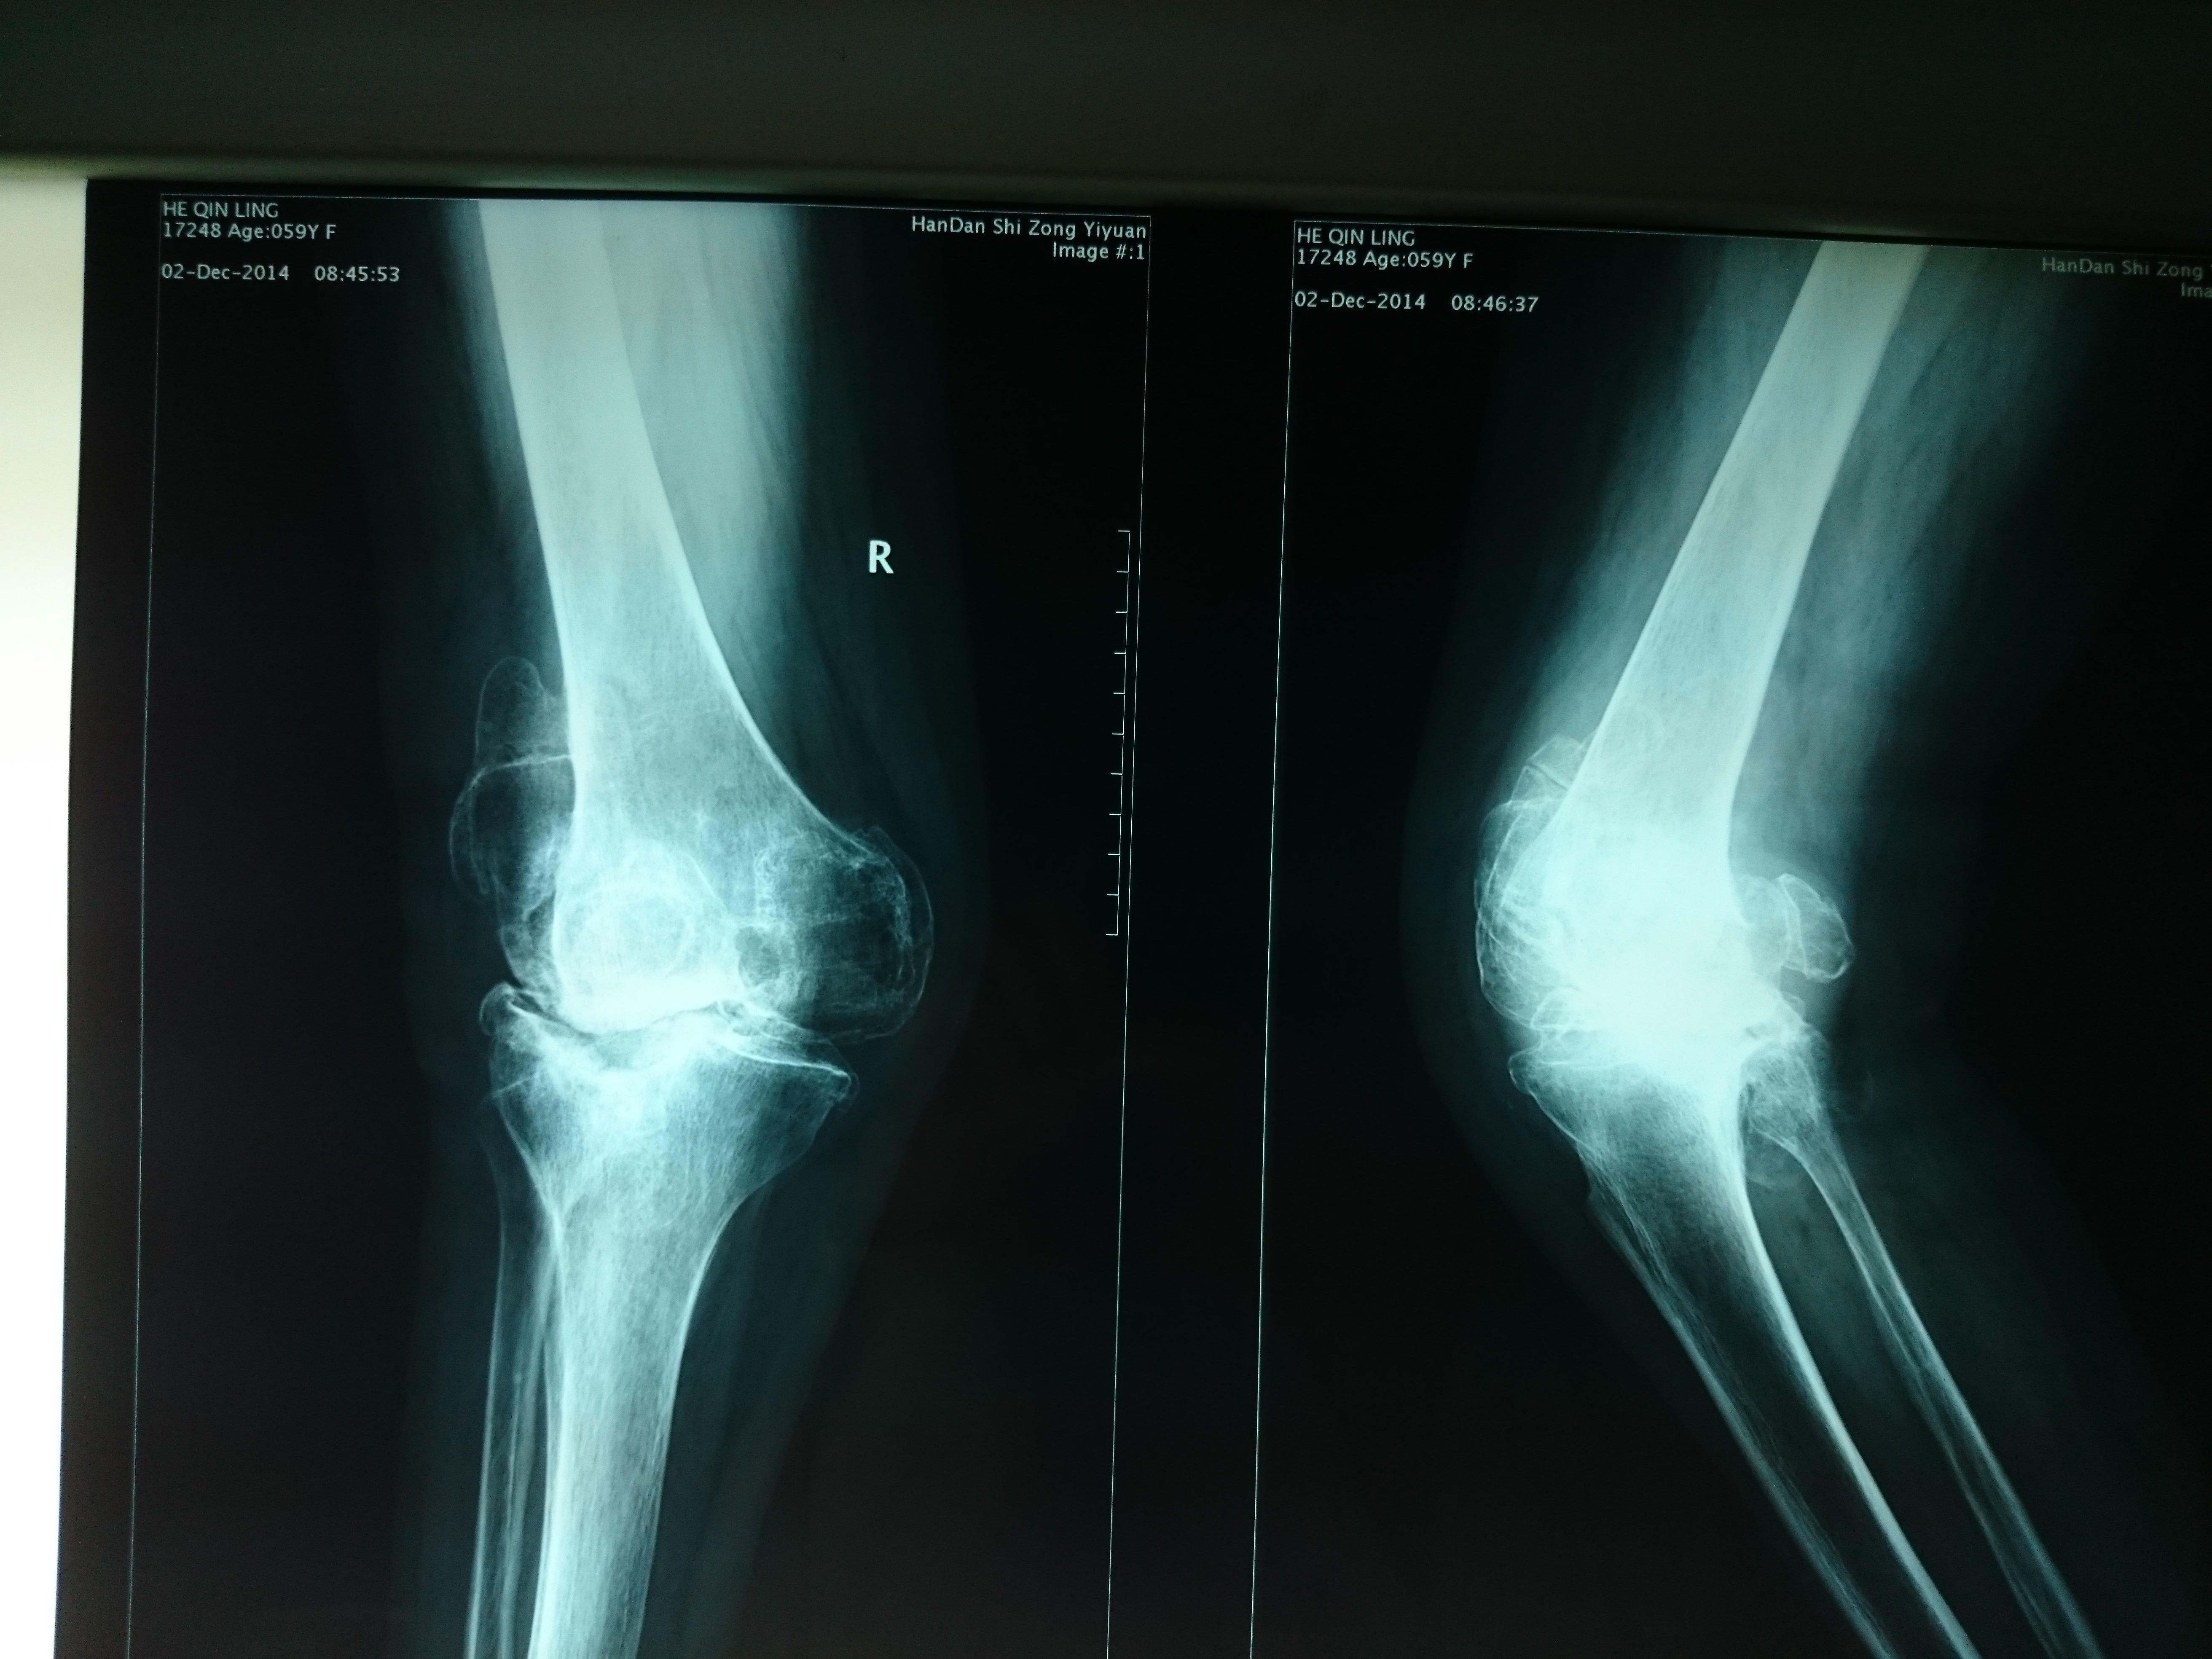

首页 > 张恒云工作室 > 影像资料 二十二